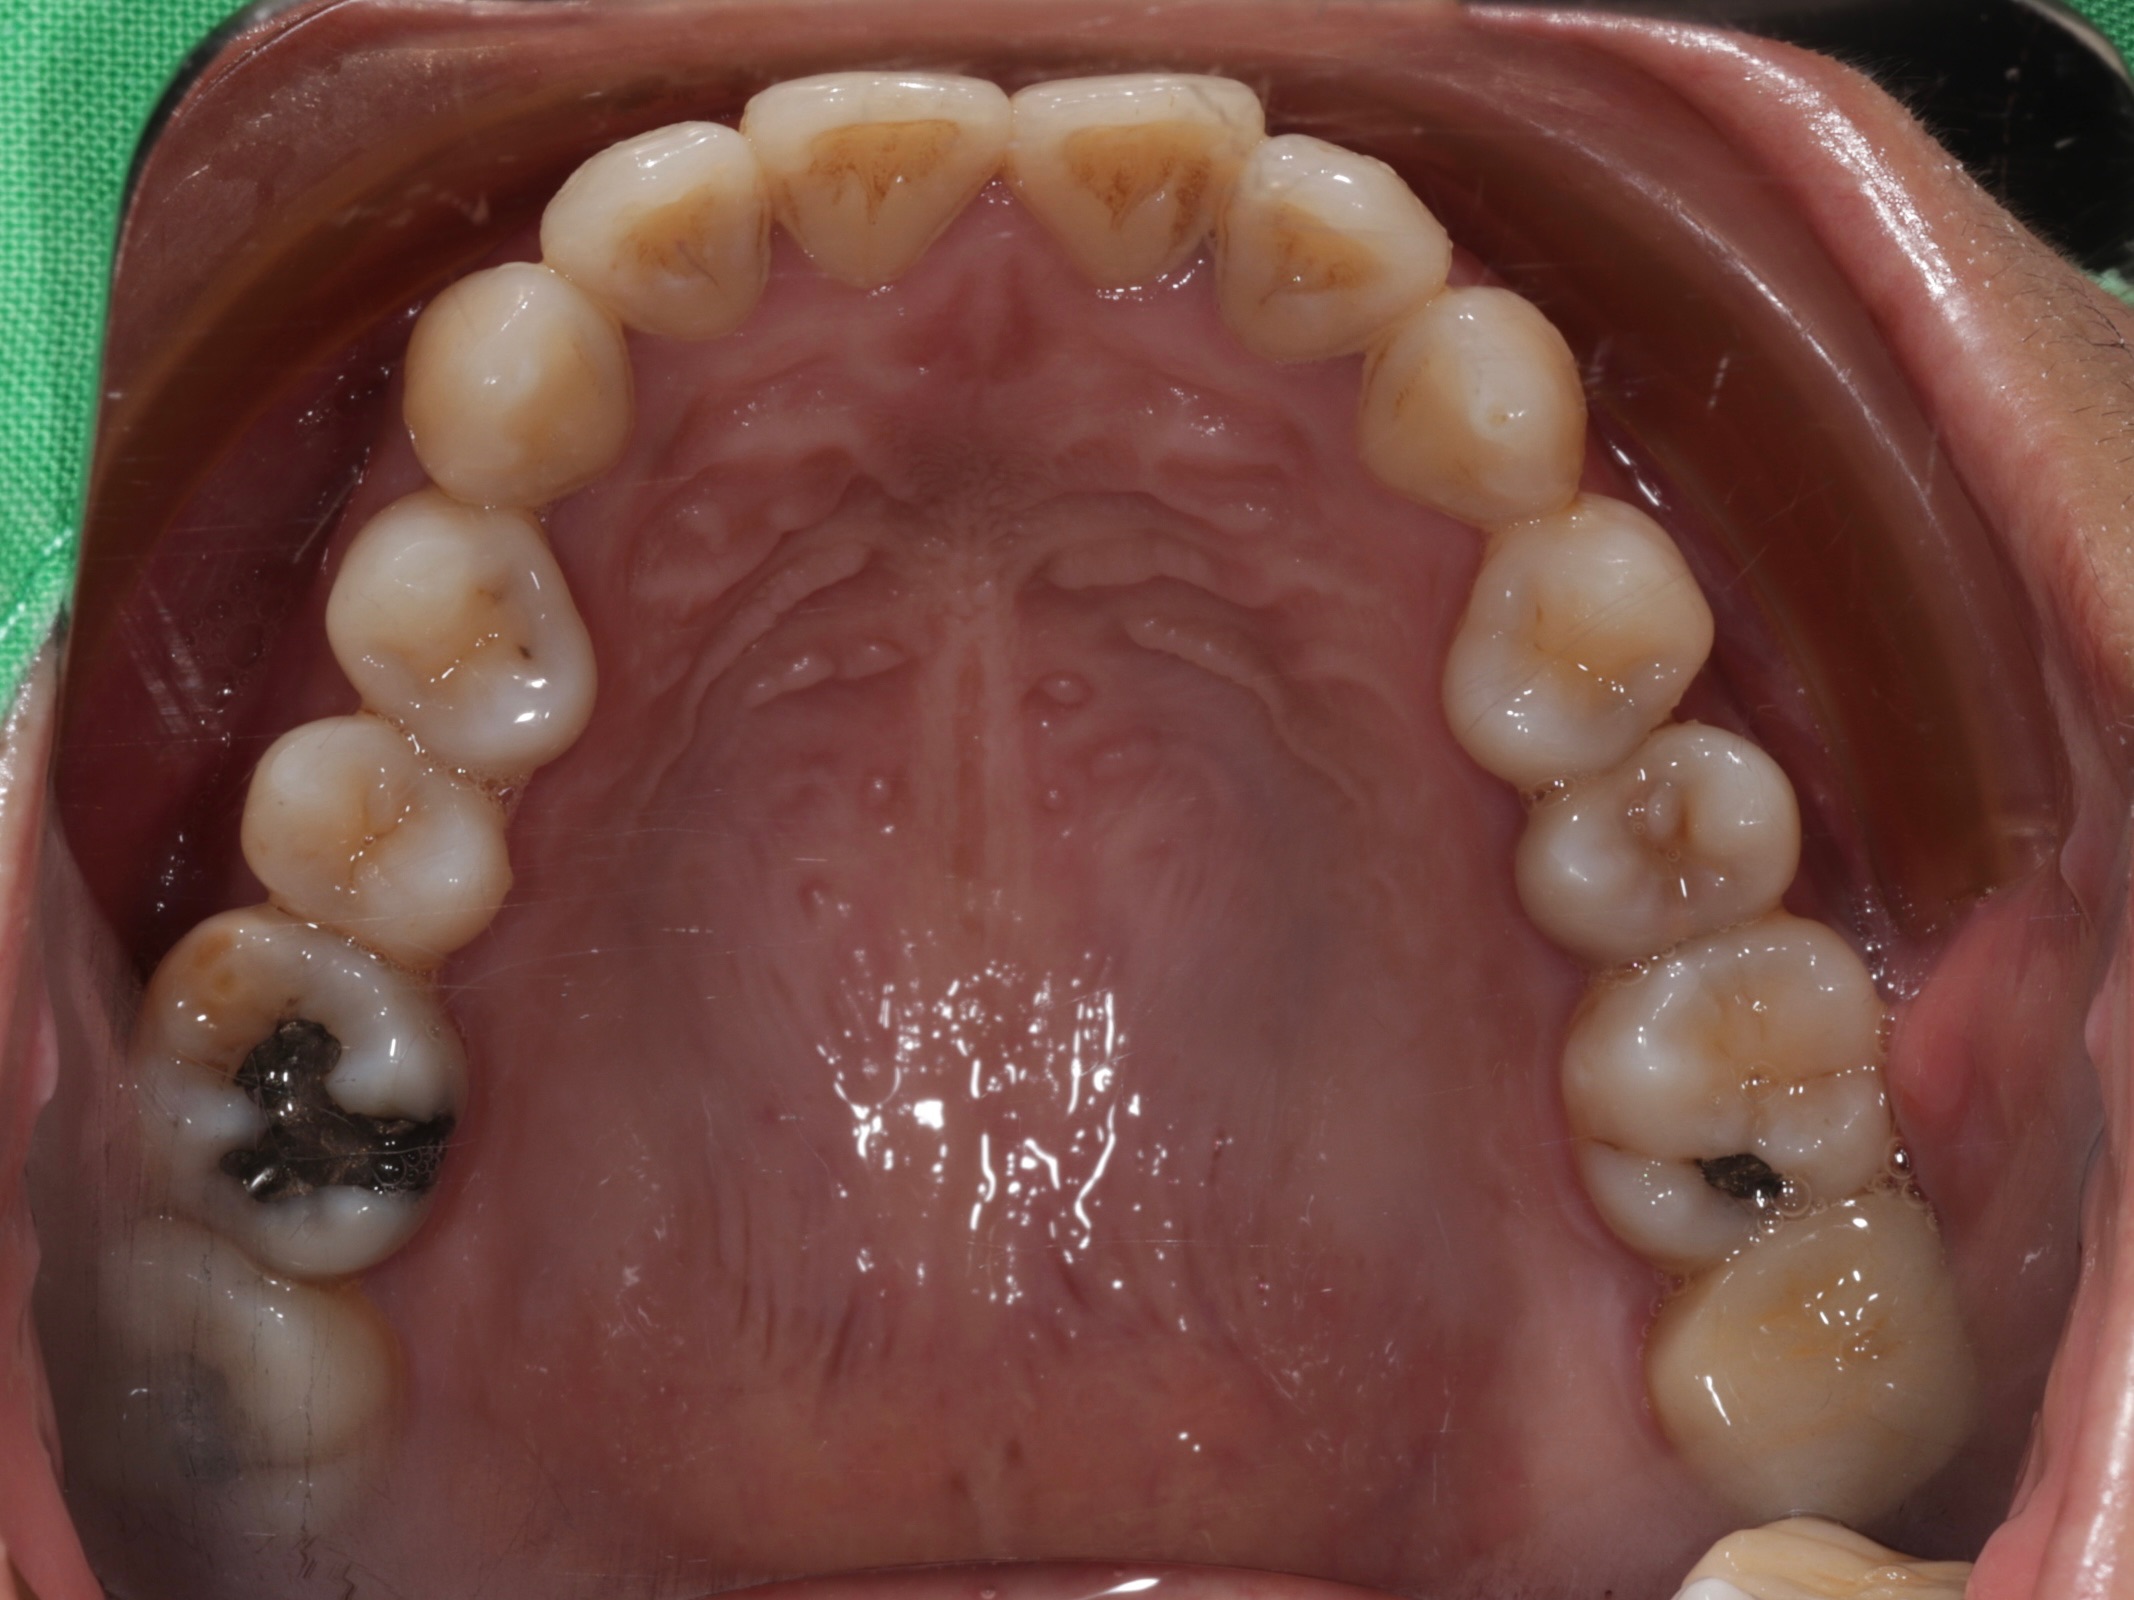

古小姐第一次來到診間時,主要是希望能做全口的詳細評估與檢查,因為她進食較黏稠的食物,牙齒容易感到疼痛,刷牙的時候容易出血,更令她困擾的問題是,她以前因為蛀牙拔掉牙齒,但沒有進行後續處理,左下方有缺牙的情況,除了導致牙齒開始出現縫隙,長期習慣用右邊進食,也讓她兩邊咬合都不太舒服。

經過全口檢查與評估後,我們發現古小姐的口腔問題相當複雜,主要可以歸納為以下幾個項目:

全口牙周病問題 - 導致刷牙時流血的主因

左邊缺牙問題 - 長期缺牙導致排列與咬合問題

咬合與牙縫問題 - 影響整體美觀與功能

我們首先進行最基本的牙周治療,控制發炎狀況,並處理蛀牙問題,為後續治療奠定良好基礎。